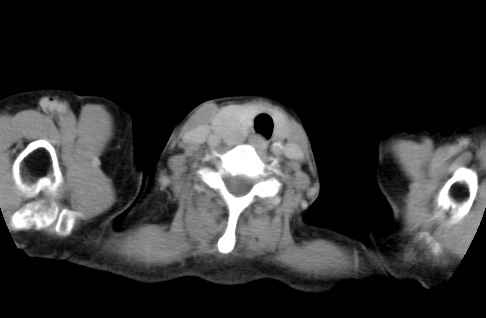

标题: CT23982:女67岁,胸部扫描时发现,甲状腺瘤? [打印本页]

标题: CT23982:女67岁,胸部扫描时发现,甲状腺瘤?

右侧甲状腺腺瘤!支持!不排除甲状腺癌可能!建议手术切除!

右侧甲状腺占位性病变,性质待定(甲状腺腺瘤?);建议:必要时行进一步检查。

右侧甲状腺占位性病变,性质待定(甲状腺腺瘤?);建议穿刺活检。

右侧甲状腺占位性病变,甲状腺腺瘤可能,建议穿刺活检。